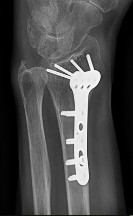

- الأشعة السينية (X-rays): هي الخطوة الأولى في تقييم الكسور، الخلوع، وتغيرات التهاب المفاصل. تساعد في تحديد مدى تدهور العظام والمسافات المفصلية. على سبيل المثال، تُظهر صور الأشعة السينية كسور السلاميات

، بالإضافة إلى علامات مثل "الدمعة الشعاعية" (Radiographic Teardrop) في الرسغ التي تمثل الزاوية الزندية الراحية الحرجة للكعبرة البعيدة

. - الأشعة المقطعية (CT Scan): توفر صوراً تفصيلية ثلاثية الأبعاد للعظام، وهي مفيدة جداً لتقييم الكسور المعقدة، مثل كسور العظم الخطافي (Hamate Hook Fracture) التي قد لا تظهر في الأشعة السينية العادية